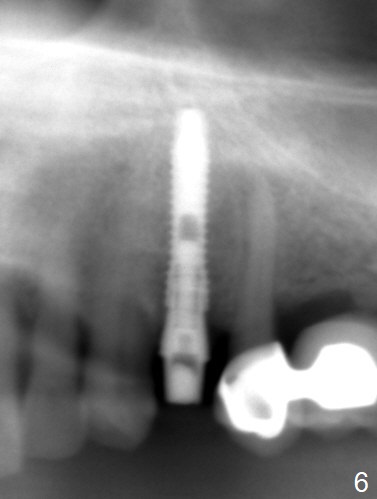

RPD Clearance